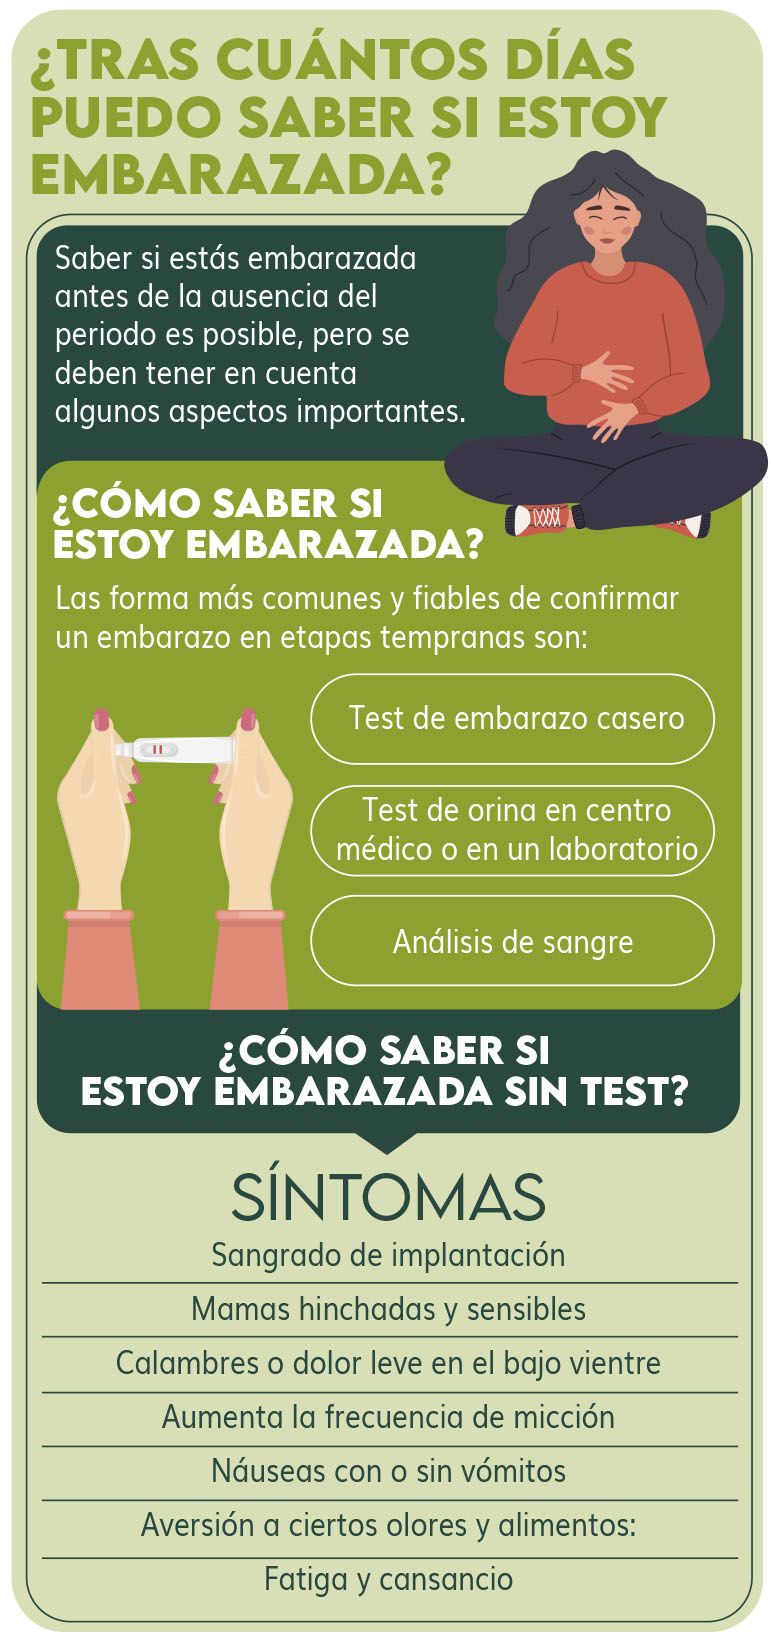

Test de embarazo como y cuando hacerlo MD.Saude hotsell, Semana 14 de embarazo sintomas y desarrollo del bebe Dodot hotsell, Calendario de Embarazo semanas 1 2 y 3 Pampers hotsell, Cuando hacer un test de embarazo para que sea fiable hotsell, Semana 14 de embarazo inicio del segundo trimestre hotsell, Creo que estoy embarazada Test de embarazo online para despejar dudas hotsell, Gestograma Calculadora semanas y dias del Embarazo Natalben hotsell, Semana 3 de embarazo inicio del desarrollo del embrion hotsell, Creo que estoy embarazada Test de embarazo online para despejar dudas hotsell, EMARLAN hotsell, Calcular la ovulacion El mejor momento para quedar embarazada YouTube hotsell, Semana 1 de embarazo cuales son los sintomas en la madre hotsell, Cuanto se tarda en lograr un embarazo tras mantener relaciones hotsell, Como saber si estoy embarazada de pocos dias 18 signos mas comunes hotsell, Sintomas de embarazo pero test negativo posible falso negativo hotsell, Como saber si estoy embarazada de pocos dias 18 signos mas comunes hotsell, Cuando hacerse un test de embarazo hotsell, Cuando hacerse un test de embarazo hotsell, Como puedo saber si estoy embarazada Centro Medico ABC hotsell, Semana 1 de embarazo cuales son los sintomas en la madre hotsell, Cuando hacer la prueba de embarazo DKV hotsell, Es posible quedar embarazada durante los dias no fertiles Next Fertility hotsell, Estoy embarazada pero nunca perdi mi periodo menstrual hotsell, Semanas 1 2 y 3 de embarazo Pampers hotsell, Cuando hacer un test de embarazo para que sea fiable hotsell, Periodo con retraso o embarazo Vamos a averiguarlo hotsell, Cuantos dias de retraso son normales para saber si estoy embarazada hotsell, Cuando hacer la prueba de embarazo DKV hotsell, Semana 2 de embarazo lo que debes saber Hero hotsell, Semana 1 de embarazo cuales son los sintomas en la madre hotsell, Semanas 1 2 y 3 de embarazo que es lo que te espera Dodot hotsell, Primeros sintomas de embarazo antes del retraso menstrual hotsell, Primeros sintomas de embarazo antes del retraso menstrual hotsell, 14 dias tras la ovulacion como detectar si estas embarazada hotsell, Cuando hacer la prueba de embarazo DKV hotsell, Product Info: En 14 dias puedo saber si estoy embarazada hotsell.

Cuando hacer la prueba de embarazo DKV- en 14 dias puedo saber si estoy embarazada

- que otros sintomas hay para saber si estoy embarazada

- 15 dias despues de tener relaciones puedo saber si estoy embarazada

- como uno hace para saber si esta embarazada

- cuanto tiempo se sabe si una mujer esta embarazada

- a los cuantos dias despues de tener relaciones se si estoy embarazada

- cuanto tiempo demora para saber si estoy embarazada

- despues de tener relaciones cuanto tiempo se si estoy embarazada